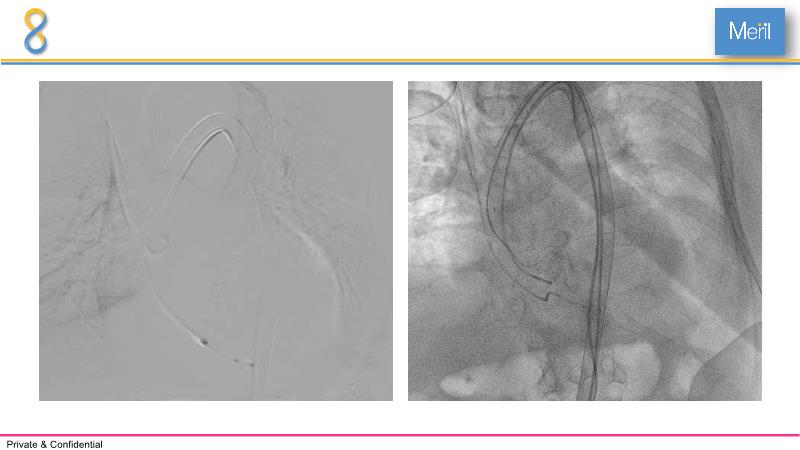

Through the presentation of several compelling cases, including an 88-year-old male with CKD, RBBB, moderate LV dysfunction, and severe aortic stenosis, a Type 1a bicuspid native AS, and an extraordinary TAVI in an 83-year-old with acute heart failure and comorbidities, this session will dive into the Myval Octapro THV. Learn about its key features, procedural impact, and potential clinical benefits. Discover the Octalign technique for predictable and precise commissural and coronary alignment, preserving coronary access. Gain insights into precise sizing, positioning, and deployment of the Myval THV series in real-world scenarios, and explore the relevance of pivotal Landmark RCTs in clinical practice.

- To understand the technique of precise sizing, positioning and deployment of Myval THV series in real world clinical scenarios